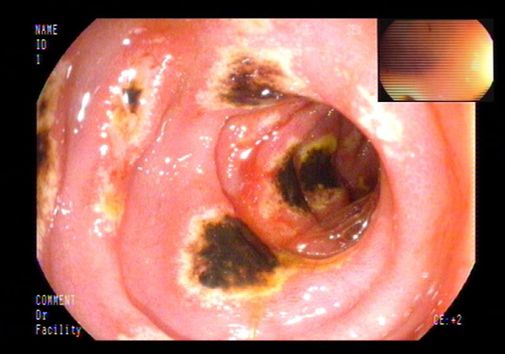

初步诊疗过程:入院后检查:血常规:单核细胞百分比 10.10%,淋巴细胞百分比 19.40%;尿常规:尿蛋白 +-;粪常规未见异常;肝功能:总胆红素 22.10umol/L,直接胆红素 12.83umol/L,谷丙转氨酶 88IU/L,谷草转氨酶 107IU/L,总蛋白 43.8g/L,白蛋白 24.3g/L,球蛋白 19.5g/L,总胆汁酸 31.4umol/L;血脂:总胆固醇 1.64mmol/L;电解质:钙 1.81mmol/L,磷 0.77mmol/L;凝血:凝血酶原时间测定 15.5秒,凝血酶原时间比值 1.46,活化部分凝血活酶时间测定 37.5秒,D-二聚体 3110.00ug/L,纤维蛋白(原)降解产物 9.56mg/L;肿瘤标志物:糖类抗原125 303.60U/ml,余项基本正常;肝炎系列+HIV+TP、T-SPOT阴性;腹水肿瘤标志物:糖类抗原125 390.10U/ml;腹水结核分枝杆菌IgG抗体阴性;复查腹水常规、生化仍提示漏出液;腹水培养阴性;PPD试验阴性;自身抗体系列未见异常。腹部超声:脂肪肝、胆囊壁毛糙、腹水;腹部血管彩超:肝段下腔静脉、门静脉及肝静脉内未见明显栓子回声。肝纤维化无创检测示:硬度值 36.5kPa。胃镜检查:食管静脉曲张、门脉高压性胃病、十二指肠多发溃疡。初步诊断为肝硬化失代偿期。给予利尿、抗感染、保肝、补白蛋白、放腹水、抑酸等治疗。患者病情无改善。

上消化道内镜: